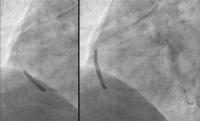

Ergebnis

Abbildung 8: Ergebnis der Stentimplantation